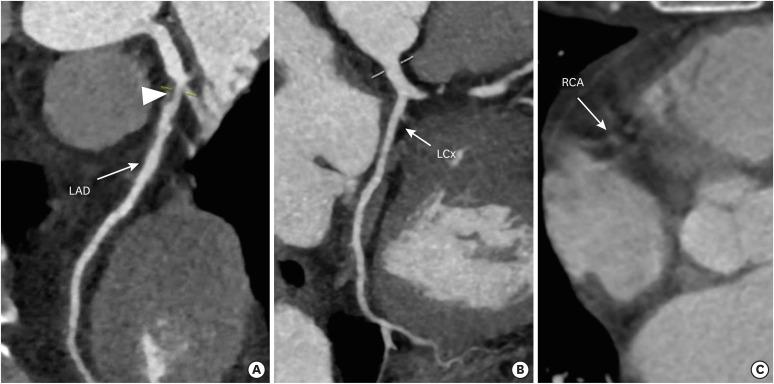

冠状动脉疾病报告与数据系统:全面综述。

Coronary Artery Disease Reporting and Data System: A Comprehensive Review.

The Coronary Artery Disease Reporting and Data System (CAD-RADS) is a standardized reporting method for coronary computed tomography angiography (CCTA). It summarizes the findings of CCTA in 6 categories ranging from CAD-RADS 0 (complete absence of coronary artery disease) to CAD-RADS 5 (total occlusion of at least one vessel). It is applied on per patient basis for the highest grade of the stenotic lesion. The CAD-RADS also provides category-specific treatment recommendations, helping patient management. The main objectives of the CAD-RADS are to improve the consistency in reporting, facilitate the communication between interpreting and referring clinicians, recommend the best course of patient management, and produce consistent data for quality improvement, research and education. However, CAD-RADS has many limitations, resulting into the misclassification of the observed findings, misinterpretation of the final category, and misguidance for the treatment based upon the single score. In this review, the authors discuss the CAD-RADS categories and modifiers, along with the strengths and limitations of this new classification system.

冠状动脉疾病报告与数据系统(CAD-RADS)是一种用于冠状动脉计算机断层扫描血管造影(CCTA)的标准化报告方法。它将CCTA的结果总结为6类,范围从CAD-RADS 0(完全不存在冠状动脉疾病)到CAD-RADS 5(至少一根血管完全闭塞)。它针对每位患者应用于狭窄病变的最高等级。CAD-RADS还提供特定类别的治疗建议,有助于患者管理。CAD-RADS的主要目标是提高报告的一致性,促进解读医生与转诊医生之间的沟通,推荐最佳的患者管理方案,并产生用于质量改进、研究和教育的一致数据。然而,CAD-RADS有许多局限性,导致观察结果的错误分类、最终类别的错误解读以及基于单一分数的治疗误导。在本综述中,作者讨论了CAD-RADS类别和修饰符,以及这个新分类系统的优点和局限性。